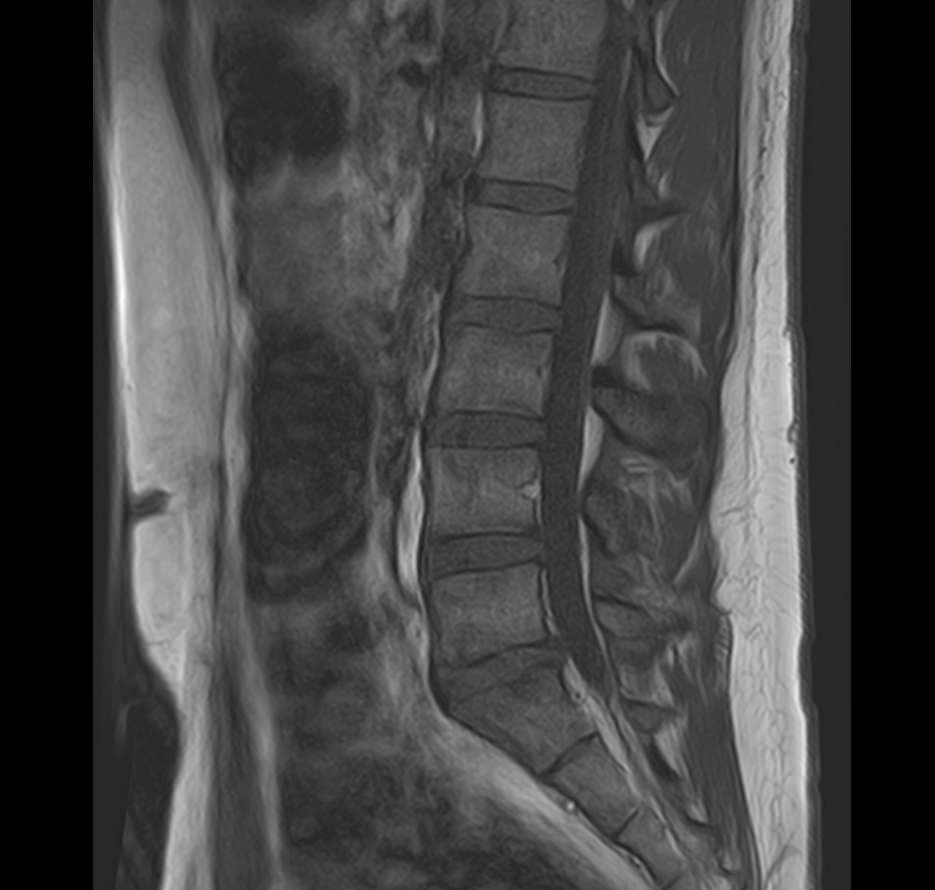

В нашей клинике мы проводим комплексное исследование, включающее МРТ головного мозга и всех отделов позвоночника. Методика комплексного обследования применяется при наличии у пациента сочетанных поражений головного мозга, спинного мозга и позвоночного столба.

При подозрении на распространенный процесс с поражением различных уровней позвоночника целесообразно проведение МРТ для диагностики дегенеративно-дистрофических заболеваний, травматических, воспалительных изменений, а также опухолевых процессов позвоночника. Метод позволяет оценить состояние структур позвонков, позвоночного канала с расположенным в нем спинным мозгом и окружающих мягких тканей, кроме того, является основным способом диагностики демиелинизирующих заболеваний спинного мозга.

Исследование проводится на современном томографе TOSHIBA VANTAGE TITAN 1,5 Тесла. За счет высокой индукции магнитного поля аппарат обладает  высокой разрешающей способностью, что позволяет проводить точную диагностику заболеваний центральной нервной системы и позвоночника.